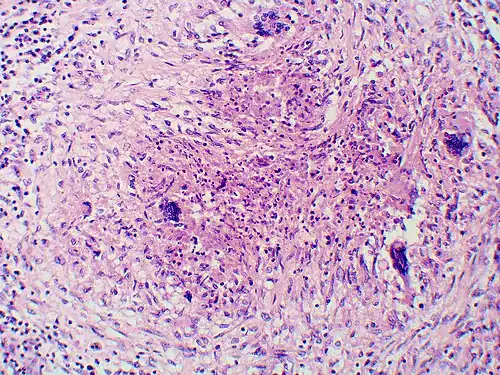

Once suspected, the diagnosis of blastomycosis can usually be confirmed by demonstration of the characteristic broad-based budding organisms in sputum or tissues by KOH prep, cytology, or histology.[27] Tissue biopsy of the skin or other organs may be required to diagnose extra-pulmonary disease. Blastomycosis is histologically associated with granulomatous nodules.

-

Granuloma with early suppuration. The fungal organisms are difficult to recognize at this low magnification. -

Large yeast-like fungi seen within giant cells at arrows. -

Large yeast-like fungi seen within giant cells at arrows. Budding yeasts in the cytoplasm of giant cells at the arrows. Broad-based budding and double-contoured cell walls are seen in the giant cell in the center are characteristic of Blastomyces dermatitidis. -